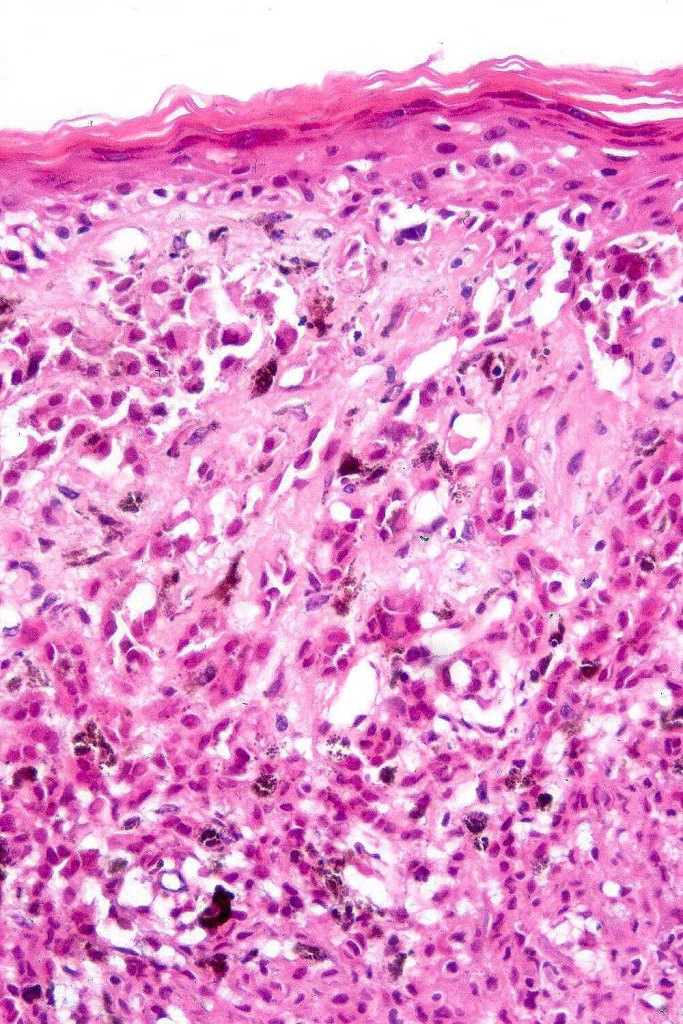

Histological features

•+/- Lentigo maligna (some examples are devoid of a junctional component)

•Lymphoid aggregates*